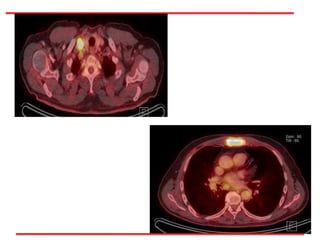

Entre el 06.02.17 – 17.02.17

Recibió 30 Gy en 10 Fx en 2s.

Concomitante RDT VMAT con CBCT diario al Tu. Pulmonar residual y

Esternon 25 Gy en 5 Fx en 2s.

Baseline Septiembre 2016 Abril 2017

Caso Clínico Entre el06.02.17 – 17.02.17 Recibió 30 Gy en 10 Fx en 2s. Concomitante RDT VMAT con CBCT diario al Tu. Pulmonar residual y Esternon 25 Gy en 5 Fx en 2s.

• 70.

• 71.

Diagnósticos Cáncer Pulmonar CélulasPequeñas etapa IV 1ª Progresión Cerebral Platino Resistente Caso Clínico